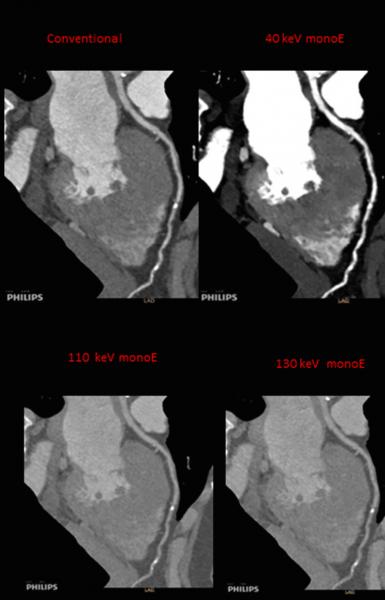

There has been a renewed interest in the development of spectral CT over the past couple years. Spectral imaging allows viewing of the same anatomy at two different kV energies. Different anatomical features are enhanced and easier to see at different energy levels. Additionally, spectral software can highlight or eliminate specific chemical compounds based on their atomic number, including iodine and calcium. This allows differentiation between calcified coronary lesions and iodine contrast in the blood vessel, or enables reconstruction of contrast and non-contrast images from a single contrast scan.

In the past, this meant using a dual-source CT scanner to image a patient at two different energy levels. Today, Philips, GE and Siemens have introduced new, single-source CT scanners that enable dual-energy imaging in a single scan. This is accomplished though dual-layer detectors with elements that absorb different energy levels and fast kV switching on the X-ray tube during scanning. The newest version of Siemens’ Somatom Definition Edge CT acquires dual-energy images using a single-source X-ray tube that emits two energy spectra simultaneously.

In September, the U.S. Food and Drug Administration (FDA) granted 510(k) for Philips’ Spectral Diagnostic Suite (SpDS), which offers a set of advanced visualization and analysis tools designed for the IQon Spectral CT technology. It allows clinicians to utilize the spectral information on-demand, without the added complexity of special modes or workstations that disrupt user workflow. Additionally, because there is no need to bring the patient back for additional imaging, on-demand spectral analysis of a particular region allows the physician to further analyze incidental findings. The package includes spectral enhanced comprehensive cardiac analysis and spectral enhanced advanced vessel analysis.